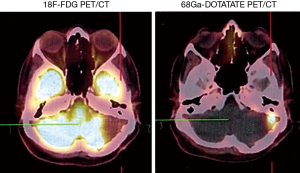

Somatostatin is a neuropeptide released by endocrine cells, neurons, and immune cells which its functions include neuroregulation (sensory, motor, and cognition) and cell growth inhibition by paracrine and autocrine pathways (37,38). Somatostatin works through a group of transmembrane G protein-coupled receptors that enter the cell following binding to specific ligands (39). So far, six subtypes of somatostatin receptors (SSTRs) are discovered including SSTR 1, 2A, 2B, 3, 4, and 5. A broad spectrum of brain tumors express different subtypes of SSTR on their surface including frequent primary brain tumors e.g., gliomas and meningiomas, pediatric brain tumors (medulloblastomas), pituitary adenomas, and supratentorial primitive neuroendocrine tumors (PNETs) (40-43). Dutour and colleague (44) have shown that gliomas and meningiomas, as the first and second most common primary brain tumors, are positive for different subtypes of SSTR. It was demonstrated that although all of them have at least one SSTR subtype, many of these harboring multiple SSTR subtypes. They provided proofs on detecting SSTRs in both tumors and their surrounding tissues, particularly blood vessels. Concerning gliomas, low-grade gliomas (WHO grade I, II) depicted higher expression levels compared to high-grade gliomas (WHO grade III, IV) (45). To date, three 68Ga-DOTA peptides are developed for clinical imaging comprised of 68Ga-DOTA-TOC, 68Ga-DOTA-NOC, and 68Ga-DOTA-TATE. The shared property of these 68Ga-DOTA peptides is the ability in binding to SSTR2, and they differ with regard to their SSTR subtype affinity and profile (Figures 4,5).